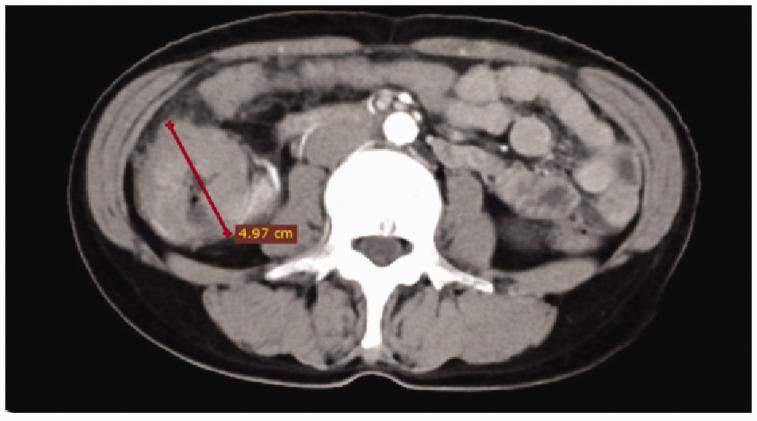

Primary colonic lymphoma is a very rare malignant tumor with no standard treatment. We report two cases of primary colonic lymphoma successfully treated with surgery and chemotherapy, and chemotherapy alone, respectively. The first case was a 61-year-old woman who presented with abdominal pain of more than 1 month. The patient was diagnosed with a colonic tumor, and immunohistochemical examinations confirmed the initial diagnosis of colonic lymphoma. The patient underwent laparoscopic-assisted right hemicolectomy followed by postoperative adjuvant chemotherapy with the cyclophosphamide, doxorubicin, vincristine, and prednisone (CHOP) regimen, combined with targeted therapy with rituximab (R-CHOP). The second case was a 78-year-old man who presented with a complaint of abdominal distention for more than 1 year. Diffuse large B-cell lymphoma was definitively diagnosed by immunohistochemical examinations, and the patient underwent systemic chemotherapy with the R-CHOP regimen. Primary colonic lymphoma is a rare type of non-Hodgkin's lymphoma (NHL), and the clinical treatment is not standardized, unlike for many other types of lymphoma. Therefore, treatment is mainly based on the patient's symptoms to determine whether surgery or systemic chemotherapy is appropriate. Rituximab is effective in some patients and may play an important role in the treatment of unresectable or asymptomatic colonic lymphoma.

原发性结肠淋巴瘤是一种非常罕见的恶性肿瘤,目前尚无标准的治疗方法。我们报告了两例成功接受手术和化疗以及单纯化疗治疗的原发性结肠淋巴瘤病例。第一例为 61 岁女性,因腹痛 1 个月余就诊。患者被诊断为结肠肿瘤,免疫组化检查明确为结肠淋巴瘤的初步诊断。患者接受了腹腔镜辅助右半结肠切除术,术后采用环磷酰胺、多柔比星、长春新碱和泼尼松(CHOP)方案辅助化疗,并联合利妥昔单抗(R-CHOP)进行靶向治疗。第二例为 78 岁男性,因腹胀 1 年余就诊。免疫组化检查明确诊断为弥漫性大 B 细胞淋巴瘤,患者接受了 R-CHOP 方案的全身化疗。原发性结肠淋巴瘤是一种罕见的非霍奇金淋巴瘤(NHL),其临床治疗方法不规范,与许多其他类型的淋巴瘤不同。因此,治疗主要根据患者的症状来确定是否适合手术或全身化疗。利妥昔单抗对一些患者有效,可能在治疗不可切除或无症状的结肠淋巴瘤中发挥重要作用。